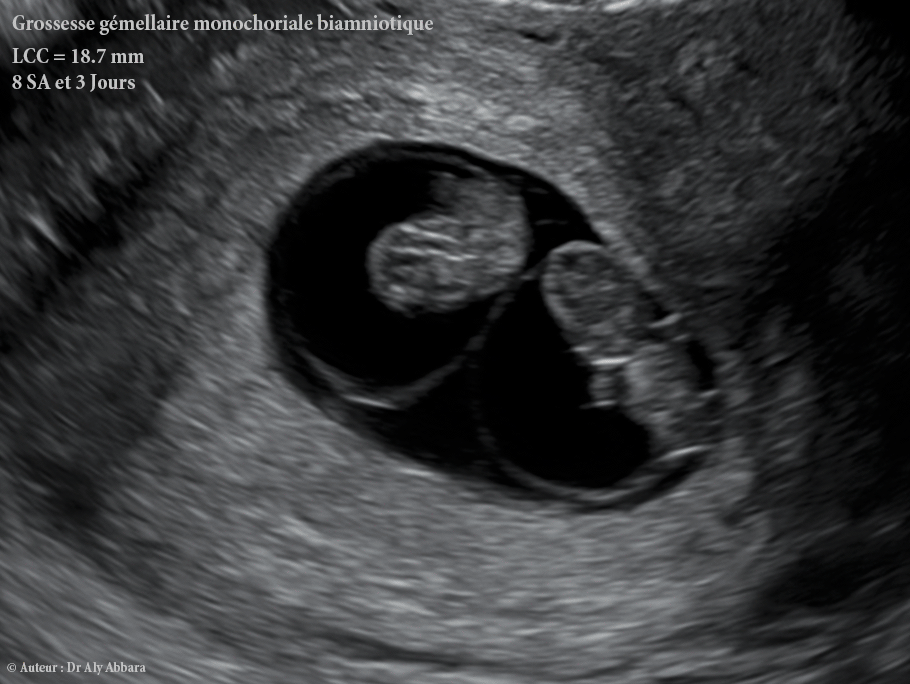

Grossesse gémellaire évolutive monozygote (vrais jumeaux), monochoriale bi-amniotique à 8 SA + 3 jours (LCC = 18,7 mm) :

- Présence d'un seul sac gestationnel entouré par un seul chorion (grossesse mono-chorial) entourant un cavité choriale unique (cavité cœlomique externe).

- Dans la cavité cœlomique externe (cavité choriale) on observe la présence de deux sacs vitellins (vésicules vitellines = vésicules ombilicales), chacun se situe à proximité d'un sac amniotique (entouré par l'amnios ou l'amnion) et contenant un embryon mesurant 18,7 mm de LCC (Longueur Crânio-Caudale) avec une activité cardiaque bien présente.

- B- Grossesse gémellaire monozygote di-amniotique monochoriale (bi-amniotique mono-choriale) :

- La division (clivage) de l'embryon survient dans un délai supérieur à deux jours et inférieur à 8 jours (ou pour certains auteurs entre le 4° et le 8° jour) par rapport à la fécondation (au stade de la morula ou blastocyste et avant la formation de l'amnios).

- Deux sacs vitellins (vésicules vitellines ou vésicules ombilicales) évoluent dans une seule cavité connue sous le nom de la cavité cœlomique externe (ou cœlome extra-embryonnaire ou encore cavité choriale).

- Échographiquement, au cours de la 5° semaine d'aménorrhée, sur la surface sphérique de chaque sac vitellin apparait d'abord un bouton (disque) embryonnaire et ensuite un sac amniotique enveloppant cet embryon.

- Dans la suite, chaque jumeau se développera dans sa propre cavité amniotique ; la membrane qui sépare les deux cavités amniotique (c'est-à-dire la cloison inter-ovulaire) est composée de deux couches qui sont les deux amnios.

- Il y a une seule masse placentaire qui se forme à partir du seul chorion existant ; dans ce cas la une circulation sanguine commune est possible par des anastomoses vasculaires artérielles ou veineuses.

- La grossesse di-amniotique mono-choriale représente 70 % des grossesses gémellaires monozygotes.